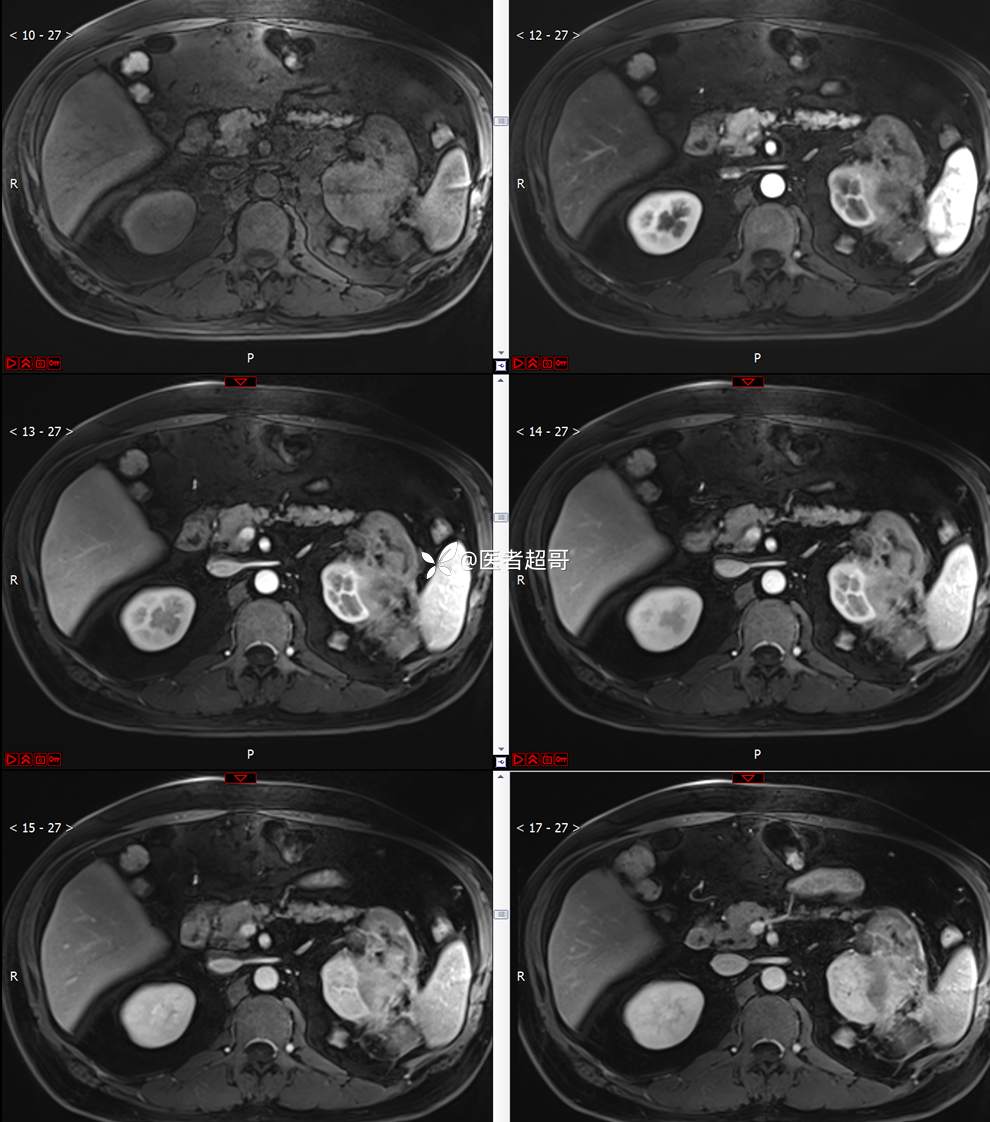

主 诉:查体发现左肾肿物9天。

现病史:患者9天前于附属医院行常规腹部CT检查时,发现左肾占位性病变并肾周脂间隙软组织增多,自述无明显腰腹部不适,无尿频、尿急、尿痛及肉眼血尿,未予特殊治疗,患者近期无头晕头迷,胸闷气急,腹胀腹泻及其他部位明显不适,遂至我院就诊,门诊以“肾肿物”收入院,患者自发病以来,精神可,睡眠饮食可,大便正常,体重无明显减轻。